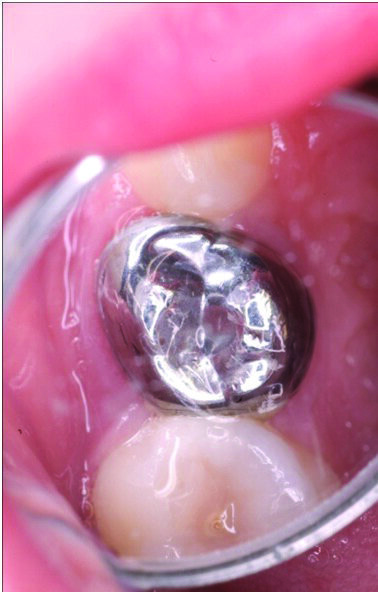

Primary tooth decay management represents a challenge for those who dentally care for children, whether they are general dental practitioners (GDPs) or specialists in paediatric dentistry. For the past 5 decades, the dental literature in the USA and Europe had advocated treating the deep carious primary molar in using the conventional “drill and fill” philosophy. That is, give local anaesthesia (LA) to the child by injection to anaesthetise the tooth, drill the carious tissue out (often after placing a rubber dam-Figure 1) using a high and slow speed drill (Figure 2), restore the primary tooth with a restorative material (often a preformed stainless steel crown or SSC) after carrying out pulp therapy (Figure 3). Although aesthetic crowns are available for primary teeth, they are very expensive and the SSC remains the crown of choice for the carious primary molar (6,7).

Figure 1: The conventional specialist approach: the child having had local anaesthesia and rubber dam placement in preparation for the restoration of 55 which had deep caries into the pulp